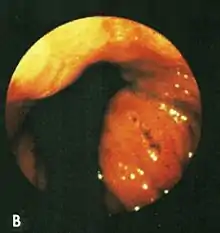

Based on their surgical observations, Windsor and Collis in 1967[4] proposed that blood loss was due to local trauma to the stomach where it rides to and fro in the hiatus on respiration. Boutelier et al.[8] noted on gastroscopy ulcers and erosions at the level of the neck of the hernia in individuals with acute and chronic bleeding, but no detailed description was given. Cameron and Higgins in 1986[1] described linear gastric erosions, later called "Cameron lesions", in people with x-rays showing one-third or more of the stomach above the diaphragm.[9][10][11][12][13][14][15] (figure 1). Over 6 years, Cameron and Higgins studied 109 persons with large hiatal hernias, 55 with anemia and 54 without anemia, at esophagogastroduodenoscopy. Cameron lesions, often multiple, were found at or near the level where the herniated stomach was constricted by the diaphragm. The lesions were typically white, superficial, linear, and oriented along the crests of inflamed appearing mucosal folds (figure 2). Small amounts of blood were often seen on the lesions (Fig 3). Mucosal folds at the diaphragm level were often seen rubbing against each other on respiration (Fig 4). It was proposed that the lesions were caused by mechanical trauma at the level of constriction by the diaphragm [1] Cameron lesions were found in 42% of persons with anemia compared to 24% in those without anemia, a statistically significant difference, p<0.05. Spots of fresh or clotted blood were seen on the lesions in 25% of persons with anemia compared to 7% without anemia, also a significant difference, p<0.05. In the 109 persons in this study, 15 had reflux esophagitis, 11 had peptic ulcers, and 7 had Barrett's esophagus, but none of these findings correlated with anemia. Thus, in people with large hernias, Cameron lesions with evidence of slow bleeding were associated with iron deficiency anemia.